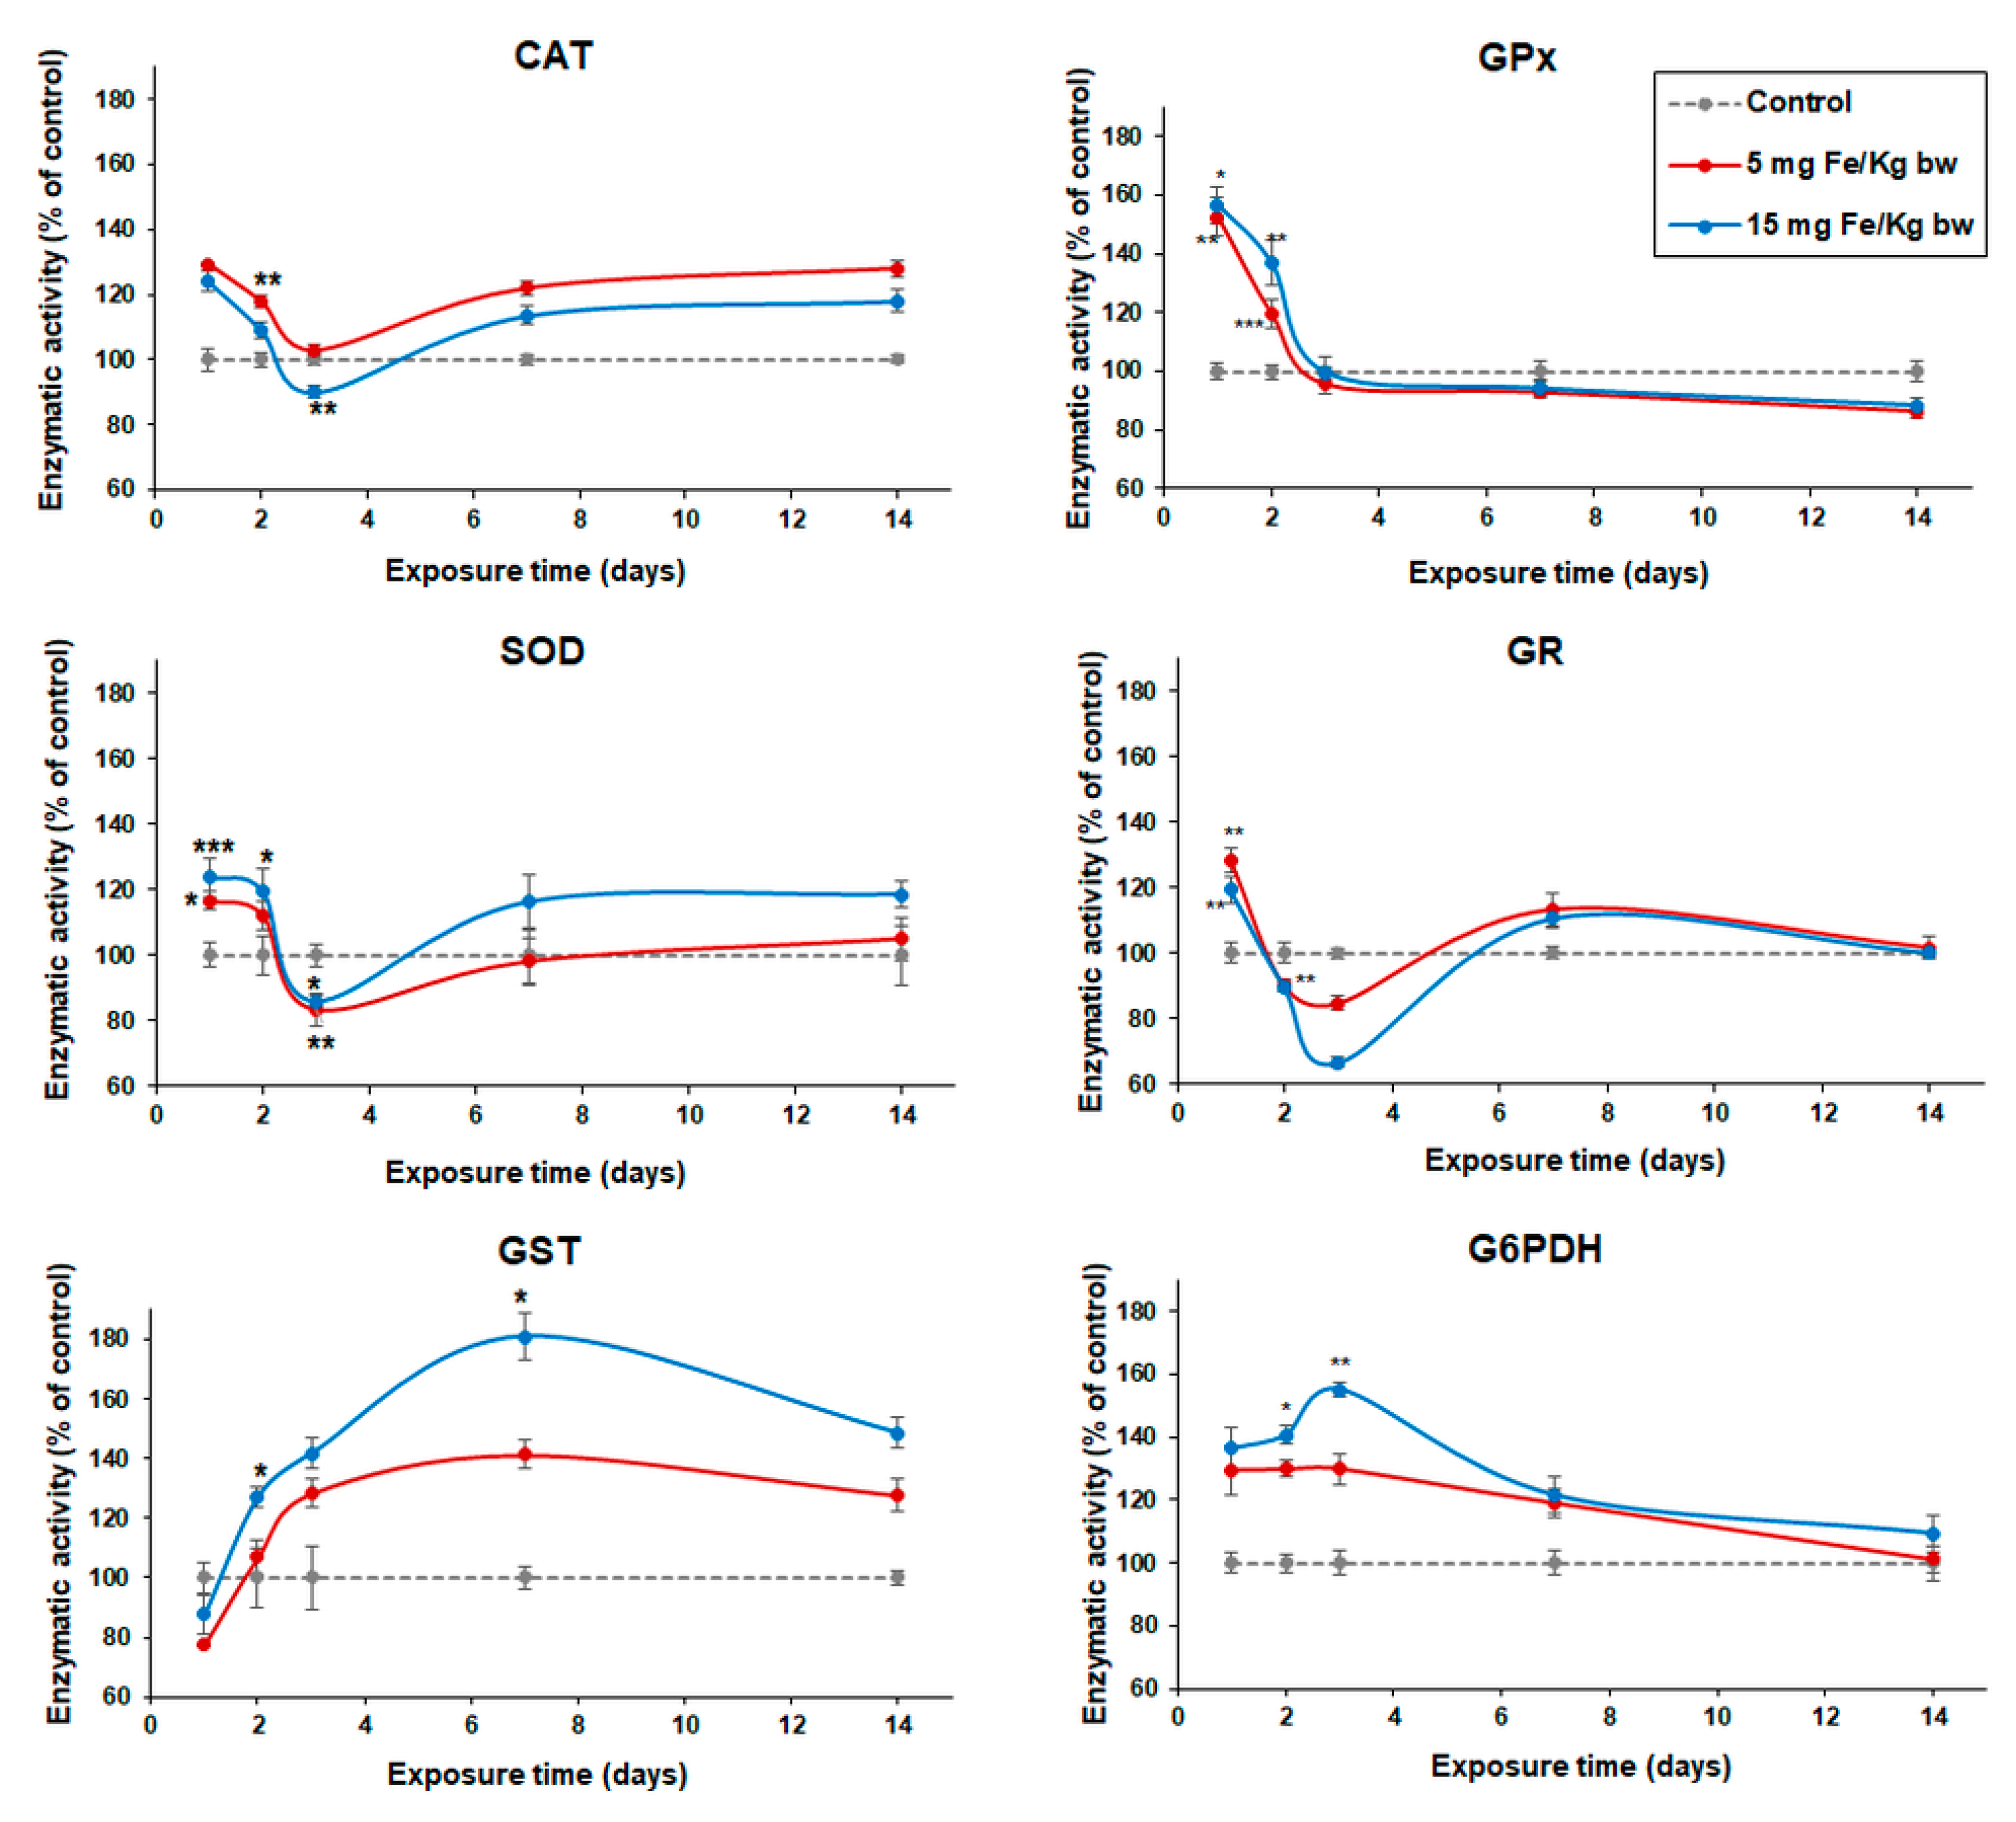

3.4. Variation of Enzymatic Activities in Mouse Liver Tissue